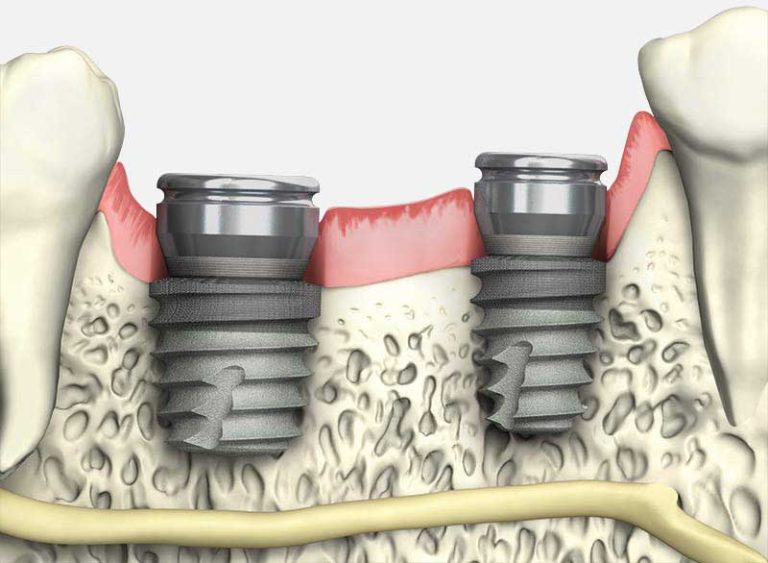

اوردنچر یا پروتز مبتنی بر ایمپلنت، جایگزینی مناسب برای دندان مصنوعی کامل است. در این روش، پروتز به جای تکیه بر لثه و بافت نرم، بر روی چند ایمپلنت دندانی (معمولاً ۴ تا ۶ پایه) قرار می گیرد. فرق دندان مصنوعی با اوردنچر را در این مقاله بخوانید. این ساختار باعث رفع مشکلاتی مانند لقی، دشواری در جویدن، کمبود استحکام و اختلال در تکلم می شود. اگر تمامی دندان های یک یا هر دو فک خود را از دست داده اید، اوردنچر می تواند گزینه ای ایده آل باشد. این نوع پروتز، نسخه پیشرفته تر دندان مصنوعی سنتی است که مزایای ایمپلنت و پروتز متحرک را ترکیب می کند و به دو شکل ثابت یا متحرک قابل استفاده است. آیا فرق اوردنچر با ایمپلنت را می دانید؟

انواع ایمپلنت های دندانی می توانند به دو روش مختلف برای نگهداری پروتز دندانی استفاده شوند: مدل های توپی و میله ای. در هر دو روش، پروتز دندان ها مشابه پروتزهای آکریلیک معمولی است، ولی دندان های پرسلن روی پایه ایمپلنت قرار می گیرند. پروتزهای میله ای به کاهش فشار و استرس وارد بر استخوان فک کمک می کنند، در حالی که پروتزهای توپی باعث ثبات بیشتر دندان مصنوعی در دهان می شوند.

- پروتز میله ای: در این روش، یک نوار فلزی که به بافت لثه جوش خورده است، به ایمپلنتی که در فک قرار دارد وصل می شود. دندان مصنوعی با استفاده از کلیپ یا سایر اتصالات به این نوار وصل می شود و در واقع پروتز روی این نوار قرار می گیرد و با کلیپ در جای خود ثابت می ماند.

- پروتزهای توپی: در این روش، هر ایمپلنت در فک دارای یک اتصال توپی است که بیرون از لثه و استخوان فک دیده می شود. این توپ در سوکت مخصوص خود در پروتز قرار می گیرد و آن را در جای خود محکم می کند. قبل از انجام این روش، دندانپزشک برای بررسی وضعیت فک و تراکم استخوان شما، رادیوگرافی می گیرد. اگر استخوان فک شما شرایط مناسب برای تحمل ایمپلنت را داشته باشد، مراحل جراحی و ساخت پروتز آغاز خواهد شد.

ایمپلنت ها قطعات فلزی کوچکی هستند که در لثه قرار می گیرند و به عنوان ریشه دندان عمل می کنند. این پایه ها از تیتانیوم ساخته شده اند که به راحتی با استخوان فک جوش می خورند و این ویژگی باعث می شود پروتزهایی که روی آن ها نصب می شوند، محکم و ثابت باشند. امروزه با پیشرفت تکنولوژی، تعداد کمتری ایمپلنت برای پشتیبانی از تعداد زیادی دندان به کار می رود، به طوری که با 4 ایمپلنت می توان تمام دندان های فک بالا یا پایین را با پروتز ثابت جایگزین کرد.

پروتزهای ثابت که بر پایه ایمپلنت نصب می شوند، گزینه ای مقرون به صرفه هستند. چرا که در صورتی که فرد تمام دندان های خود را از دست داده باشد، استفاده از پایه ایمپلنت برای هر دندان جداگانه هزینه بر و غیر منطقی است. بنابراین بهتر است از تعداد کمتری پایه ایمپلنت برای نگه داری چندین دندان استفاده کرد. هنگامی که برای ایمپلنت به متخصص ایمپلنت مراجعه می کنید، او از شما عکس های سه بعدی از لثه و دهان گرفته تا بتواند دقیقاً محل های مناسب برای قرار دادن ایمپلنت ها را تشخیص دهد.

- ایجاد حفره در لثه: برای قرار دادن ایمپلنت ها، لازم است در لثه و استخوان فک حفره ای ایجاد شود. معمولاً متخصصان برای این کار از بی حسی موضعی استفاده می کنند تا بیمار هیچ دردی احساس نکند. پس از نصب پایه های ایمپلنت، دندان های موقتی روی آن ها قرار می گیرند تا این پایه ها به طور کامل در استخوان فک جوش بخورند که معمولاً این فرآیند حدود سه ماه طول می کشد. پس از این مدت، بیمار قادر خواهد بود با دندان های جدید خود غذا بخورد. البته برای اطمینان بیشتر، توصیه می شود که تا شش هفته از جویدن غذاهای سفت و محکم خودداری کنید.